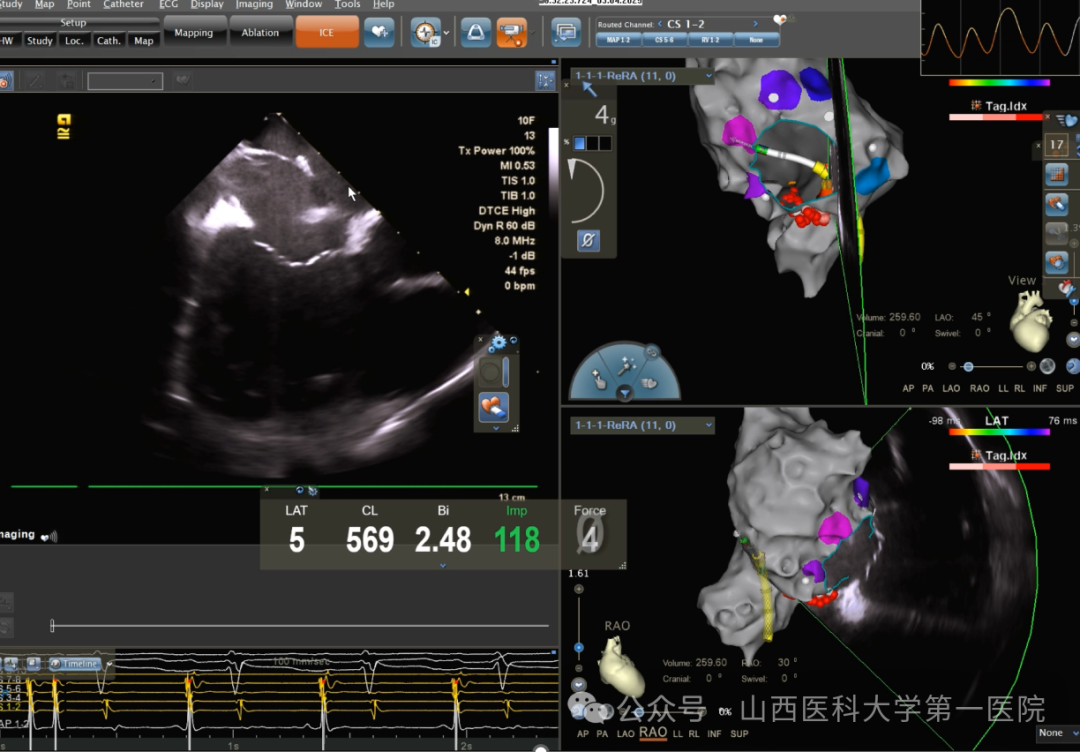

该患者主因“心悸、气短10余天”入院,心腔内电生理检查为围绕三尖瓣环折返的典型房扑。手术过程中导管压力提示存在异常结构,进行标测发现存在一结构连接下腔静脉与房间隔,根据解剖关系推测可能是下腔静脉瓣(欧式瓣)。心腔内超声(ICE)观察下,患者下腔静脉瓣畸形,与房间隔相连接,阻碍正常导管到位。标测发现,该欧式瓣与房间隔、窦口(CS-56)附近的连接处存在大量双电位现象,表明该下腔静脉瓣可能与TT腱相连,形成了线性阻滞的天然屏障,造成了电位时差。